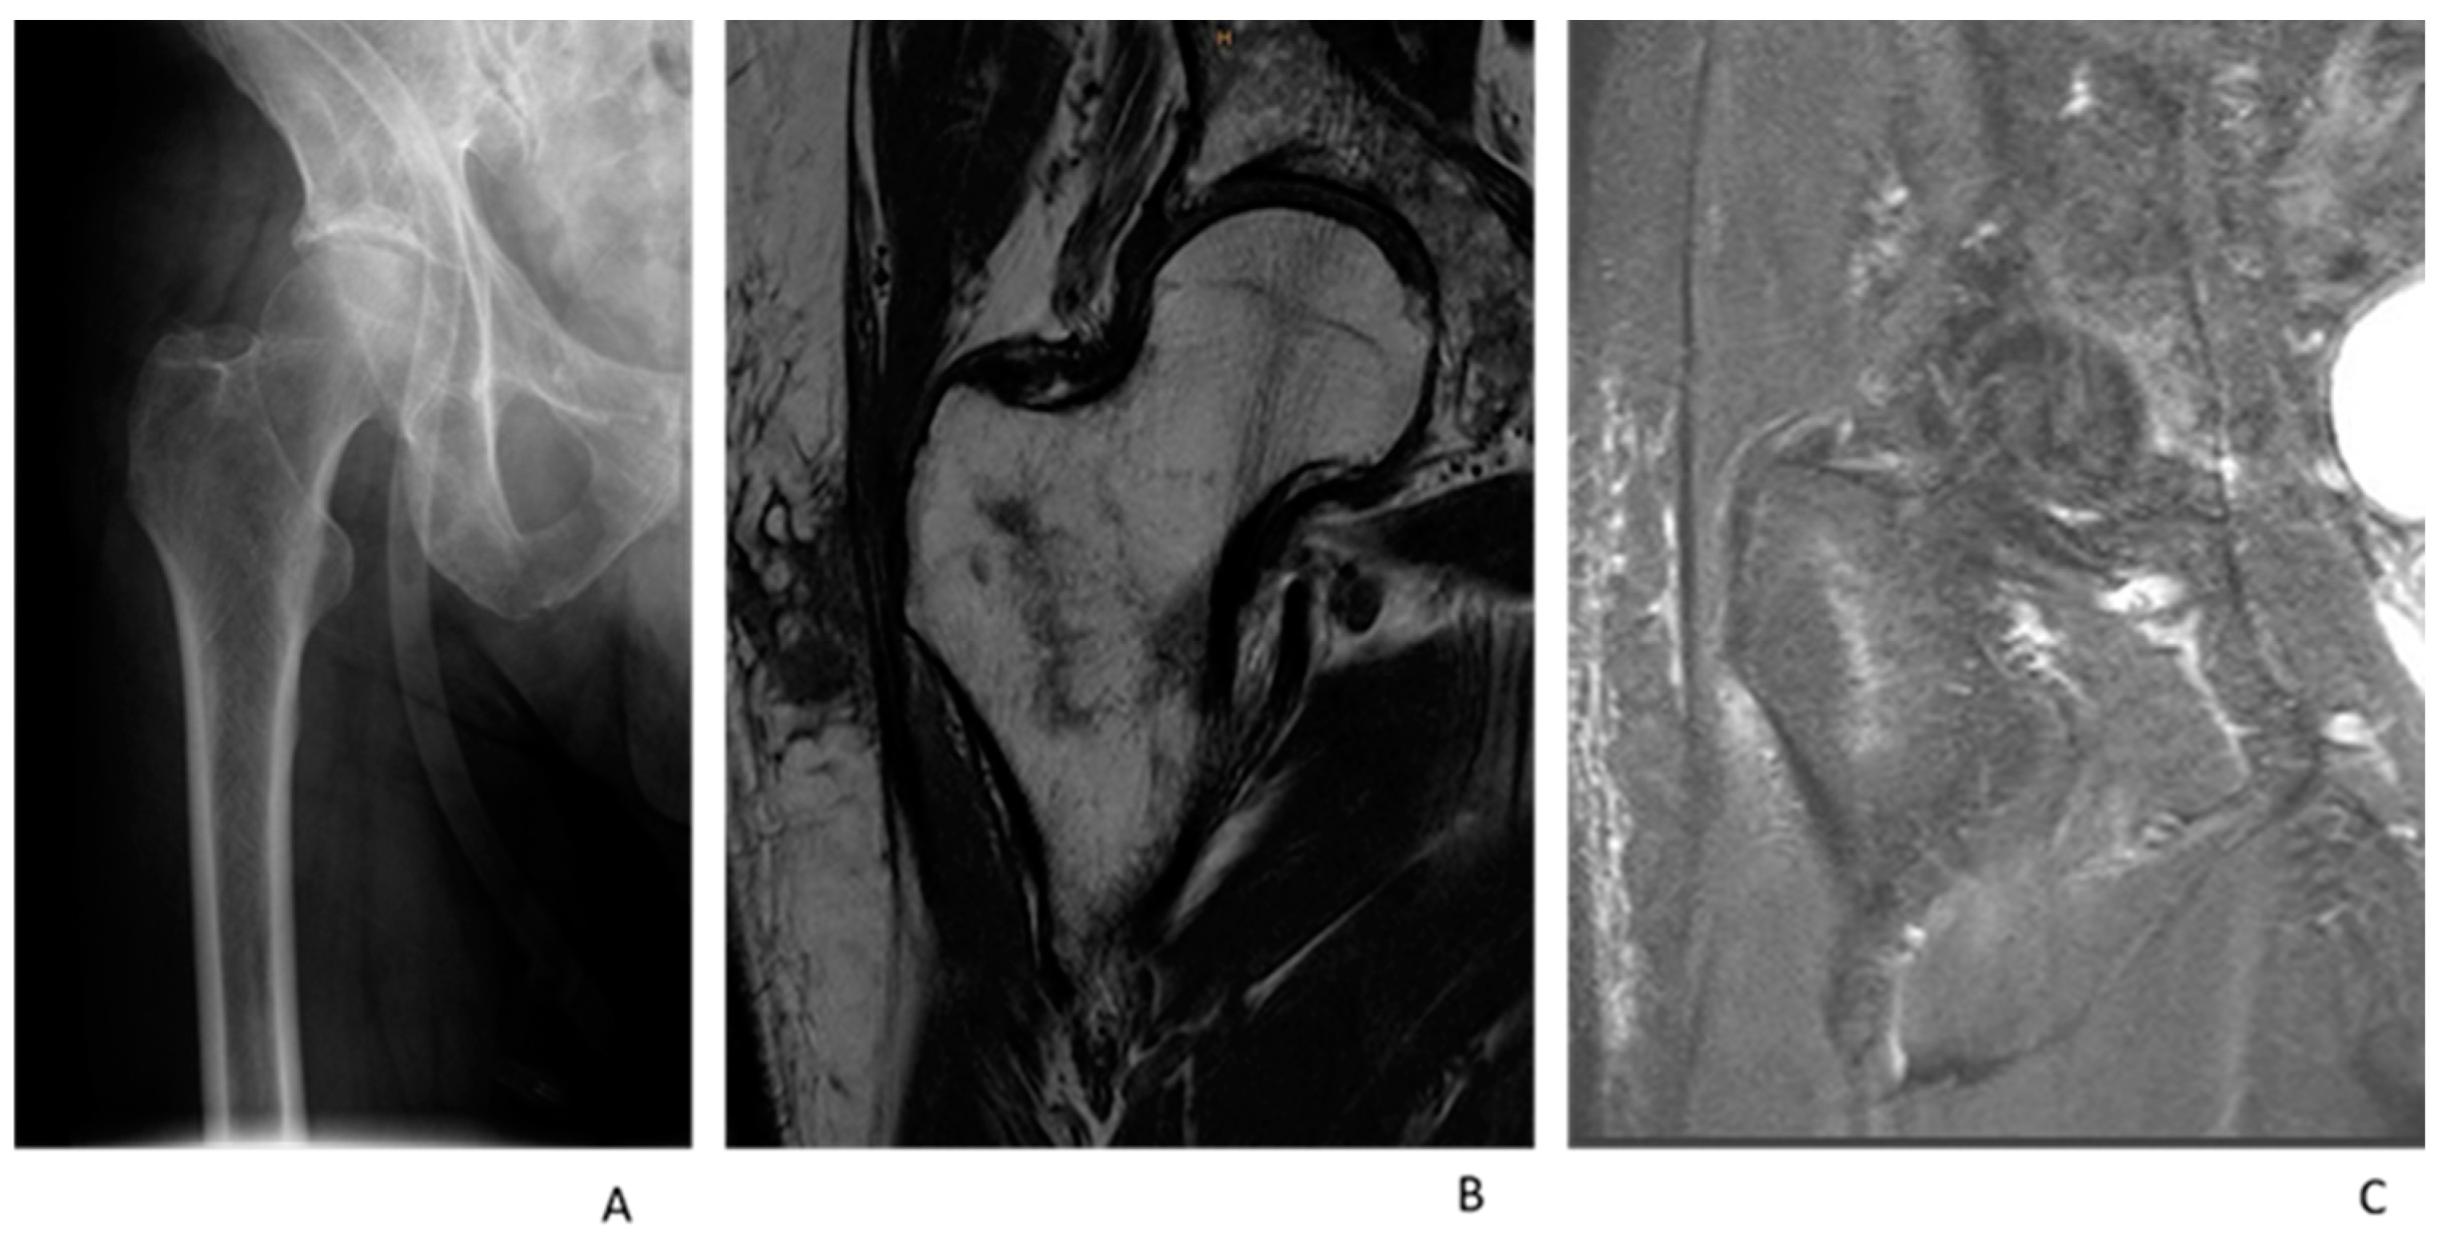

2.3. MRI